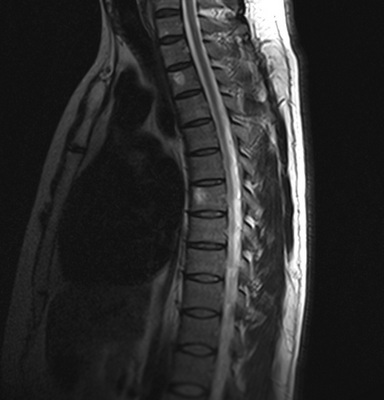

Гигантская грыжа поясничного отдела позвоночника на МРТ

МРТ активно используют для уточнения природы заболевания, обнаружения изменений в позвоночном канале. Метод позволяет выявить опухоли, грыжи дисков, образование секвестров, компрессию спинного мозга или нервных корешков. Показаниями для проведения МР-сканирования являются:

Множественные (2) гемангиомы на МРТ грудного отдела позвоночника